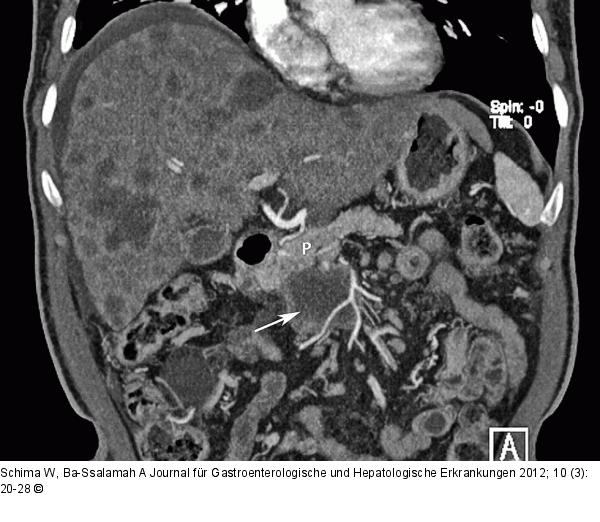

Abbildung 9: Pankreas - Adenokarzinom Adenokarzinom des Pankreas. Die 3D-Rekonstruktion der MDCT zeigt den vom Proc. uncinatus (Pfeil) des Pankreas (P) ausgehenden Tumor, der die A. mes. sup. umwächst (Stadium T4). Es finden sich multiple Lebermetastasen (Stadium M1). |

Adenokarzinom des Pankreas. Die 3D-Rekonstruktion der MDCT zeigt den vom Proc. uncinatus (Pfeil) des Pankreas (P) ausgehenden Tumor, der die A. mes. sup. umwächst (Stadium T4). Es finden sich multiple Lebermetastasen (Stadium M1). |